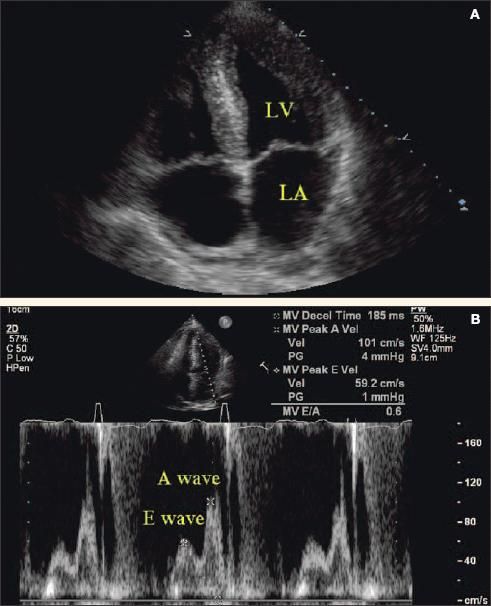

The most common causes of HFNEF are coronary artery disease, hypertension, aging, obesity, and aortic stenosis. The diagnosis is based on the presence of heart failure symptoms in the absence of depressed ejection fraction. An echocardiogram with Doppler studies can be useful in diagnosing diastolic dysfunction. The E/A ratio, in which E denotes the early peak mitral diastolic inflow velocity and A denotes the late diastolic peak mitral inflow velocity, can be useful.

Under normal conditions, E is greater than A and the E/A ratio is approximately 1.5. In early diastolic dysfunction, relaxation is impaired and there is vigorous atrial contraction, resulting in an E/A ratio of less than 0.75 (Figure 1). As the disease progresses, left ventricular (LV) compliance is reduced further, which increases early LV filling despite impaired relaxation, resulting in pseudonormalization of the E/A ratio to 1.5. In severe diastolic dysfunction, the E/A ratio is greater than 2 as a result of the LV filling occurring primarily in early diastole.22

Figure 1 – Severe left ventricular hypertrophy and grade 1 diastolic heart failure are revealed by echocardiography and Doppler ultrasonography. The apical 4-chamber view shows a thickened left ventricular wall and enlarged left atrium (A). Doppler evaluation shows impaired early diastolic relaxation (E wave) and vigorous atrial contraction (A wave) resulting in an E/A ratio of less than 0.75, which signifies early reduced left ventricular compliance (B). A normal E/A ratio is greater than 1.5, since most of the diastolic filling occurs early in a compliant left ventricle with the atrial component contributing a smaller volume at a lower velocity. (LV, left ventricle; LA, left atrium.)